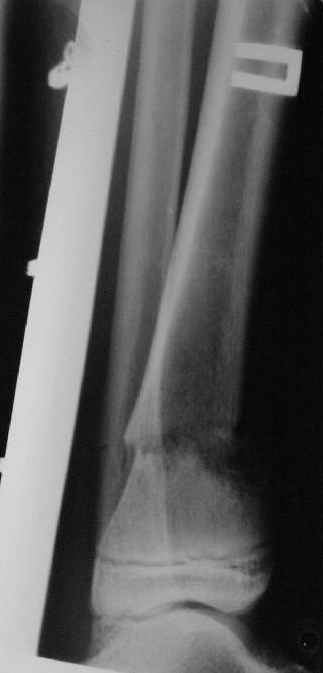

A> В январе 2005: варусная деформация н\3 голени,

A> Операции: 1 Клиновидная резекция на вершине деформации м\берцовой кости.

A> 2 Тугоподвижный ложный сустав н\3 б\берцовой кости.

Промежуточный

|